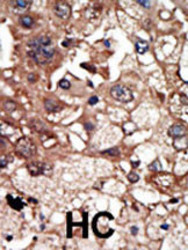

AP8148a IHC

Immunohistochemistry